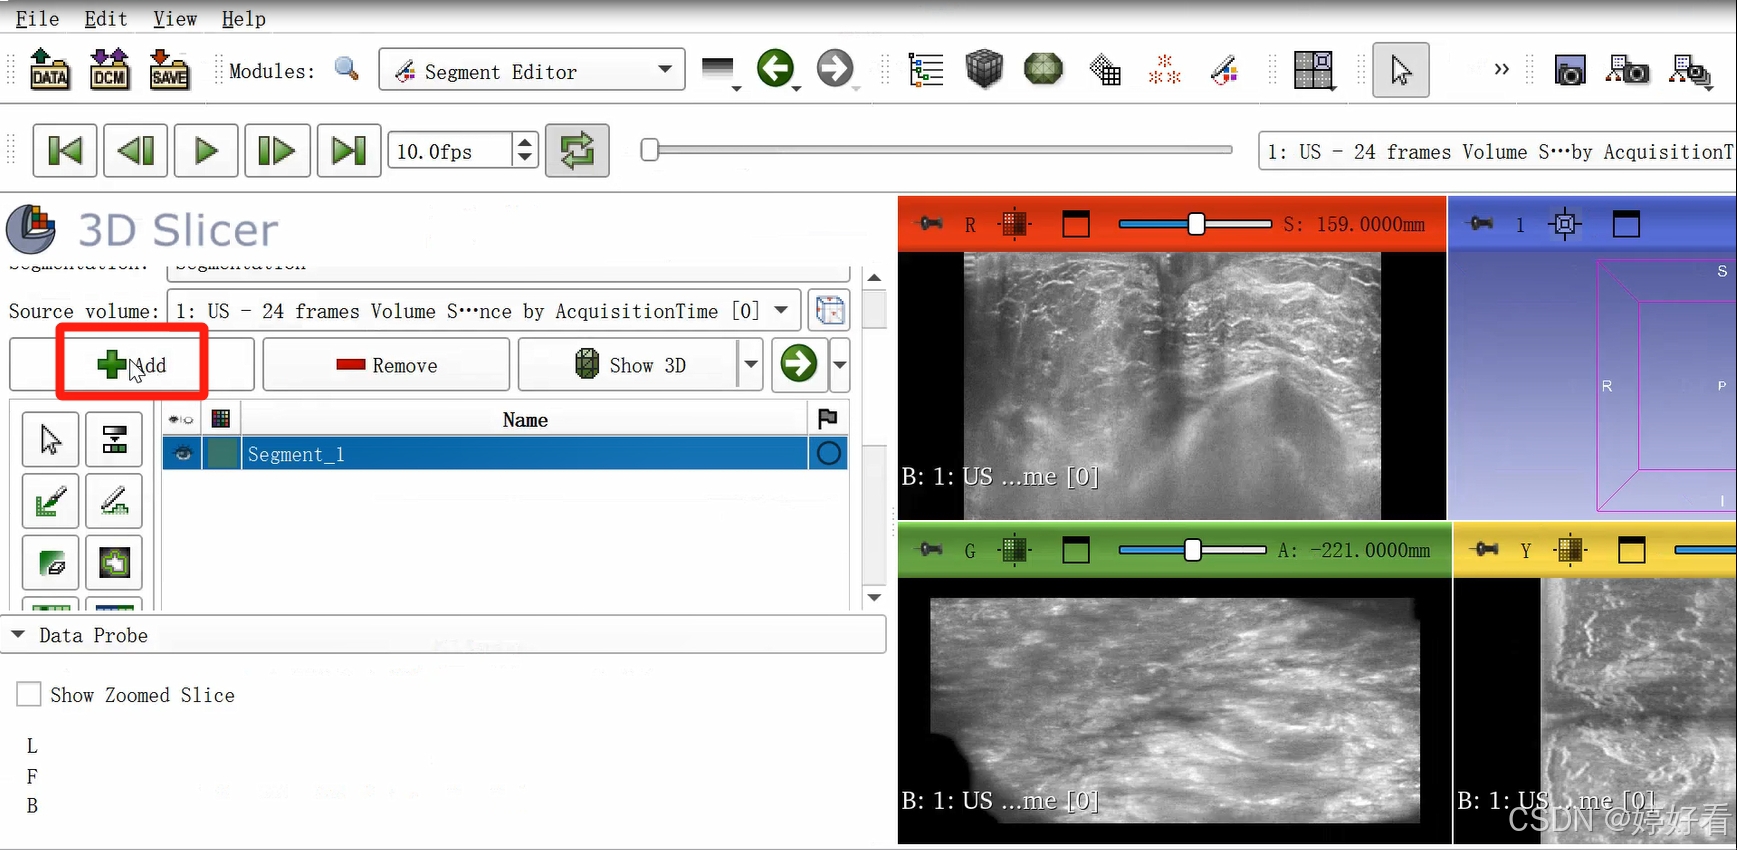

2.2 点击带有绿色“+”号的add。

2.3 使用Paint功能勾画感兴趣区域。

可以隔两三层画一次(示例中为随意勾画,大家在实际操作中可以请专业的医生确认感兴趣区域)。

这是一个三维的图像,我们只要在一个面上勾画就可以了,另外两个面会自动显示勾画的区域。